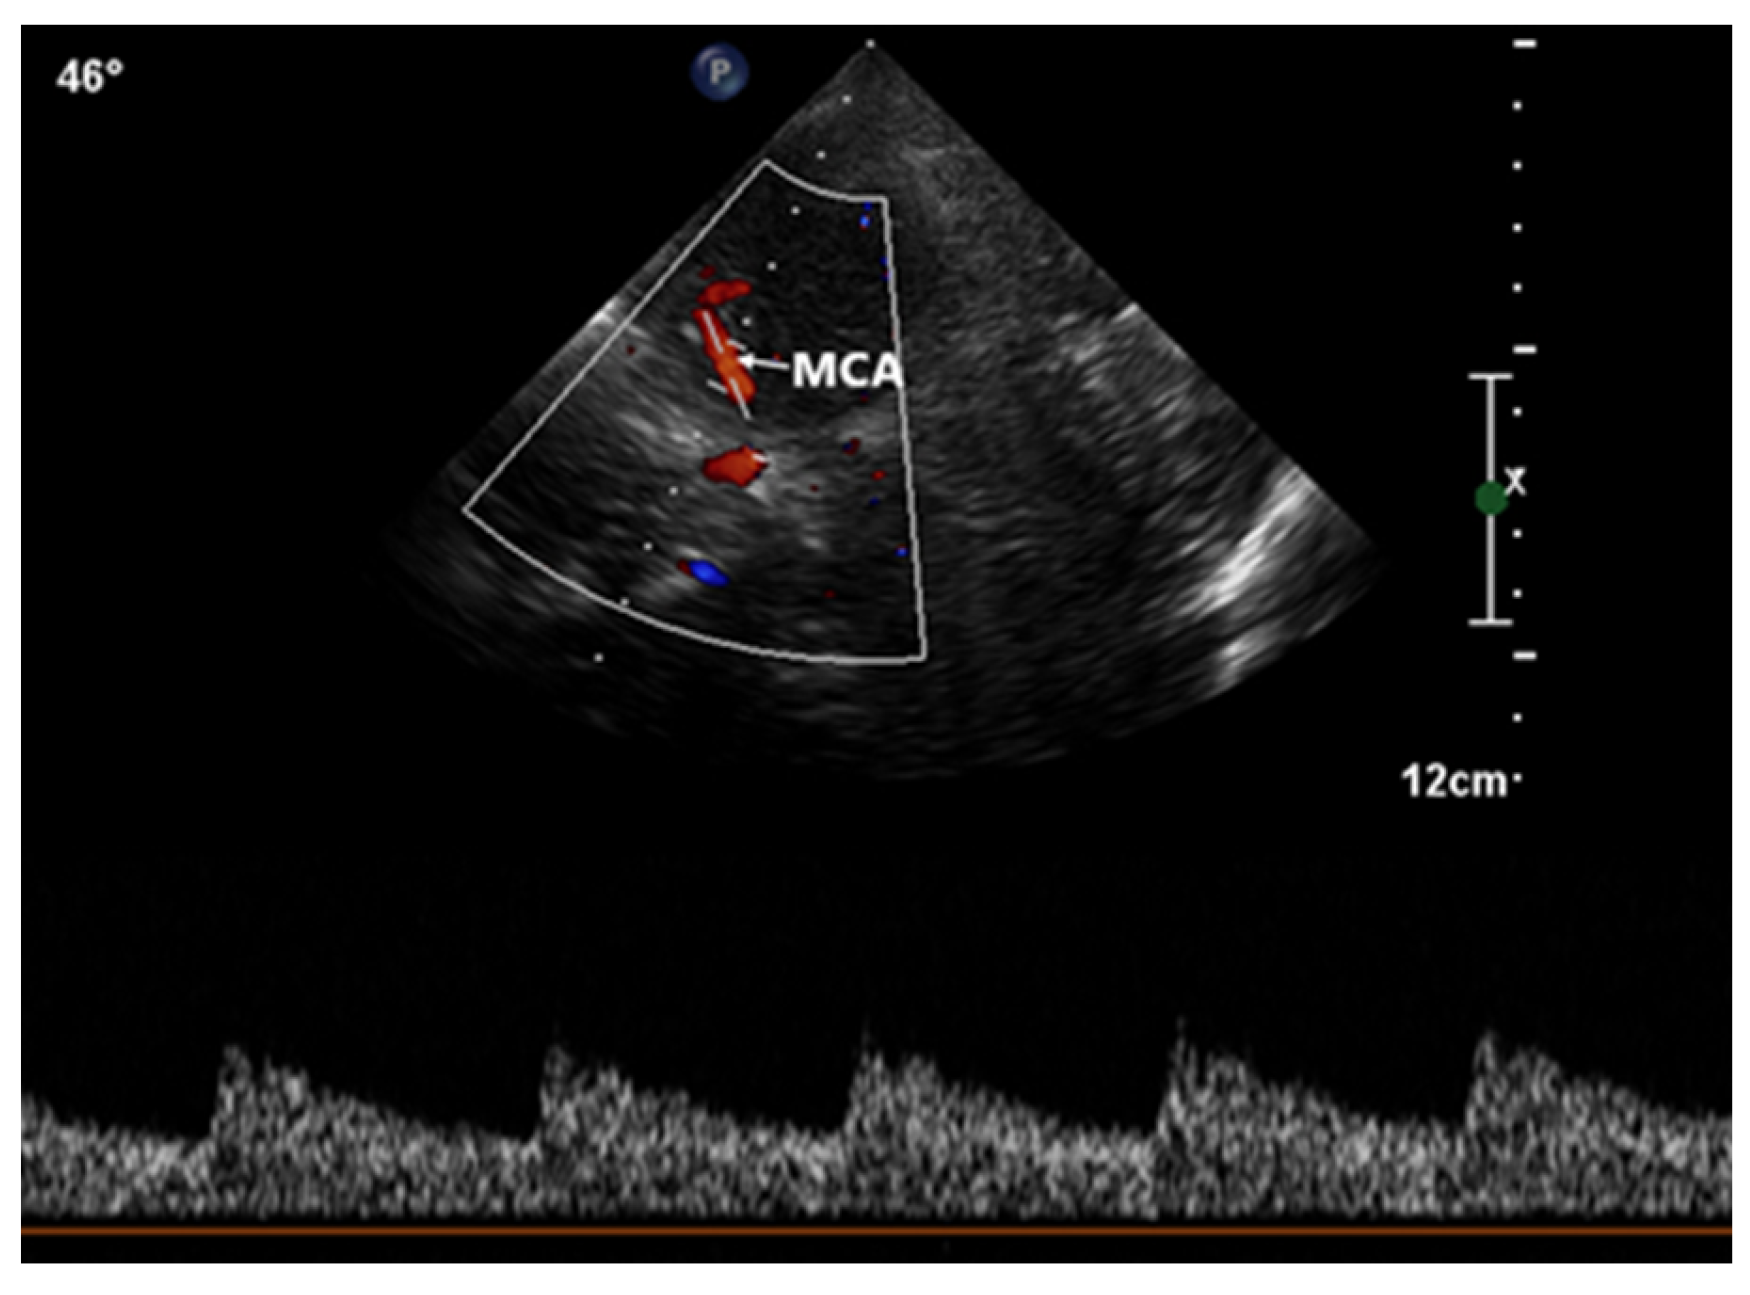

Normal transcranial Doppler. Color Doppler imaging of the left middle Transcranial Doppler With Bubble transcranial doppler (tcd) bubble test can detect or rule out pfo with a sensitivity of 97% and specificity of 93% compared with tee (18,. an intracranial neurovascular exam is also known as a transcranial doppler (tcd) study. during bubble study, the spectral doppler easily detects air bubbles that pass through the cerebral arterial circulation (such as the. Transcranial Doppler With Bubble.

we read with interest the recent article by romero et al highlighting ischemic cerebrovascular complications. during bubble study, the spectral doppler easily detects air bubbles that pass through the cerebral arterial circulation (such as the mca). transcranial doppler is utilized to investigate the intracranial vasculature for various purposes. an intracranial neurovascular exam is also known as a transcranial doppler (tcd) study. transcranial doppler (tcd) bubble test can detect or rule out pfo with a sensitivity of 97% and specificity of 93% compared with tee (18,. most experts think that a better way to assess whether a pfo is likely to produce a stroke is to do a transcranial doppler study (tcd) with a bubble.

Transcranial Doppler With Bubble transcranial doppler is utilized to investigate the intracranial vasculature for various purposes. an intracranial neurovascular exam is also known as a transcranial doppler (tcd) study. transcranial doppler is utilized to investigate the intracranial vasculature for various purposes. we read with interest the recent article by romero et al highlighting ischemic cerebrovascular complications. transcranial doppler (tcd) bubble test can detect or rule out pfo with a sensitivity of 97% and specificity of 93% compared with tee (18,. most experts think that a better way to assess whether a pfo is likely to produce a stroke is to do a transcranial doppler study (tcd) with a bubble. during bubble study, the spectral doppler easily detects air bubbles that pass through the cerebral arterial circulation (such as the mca).